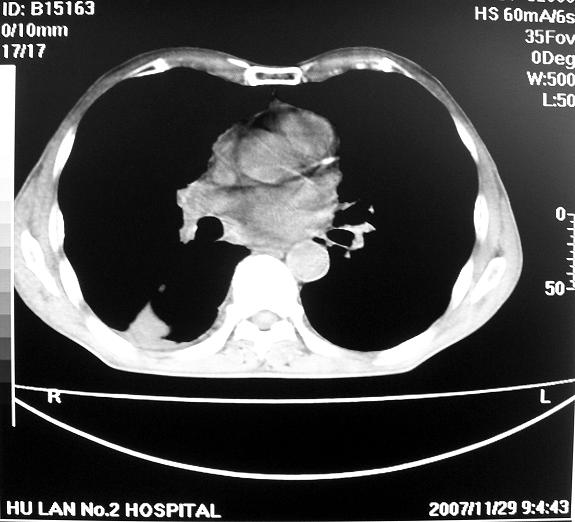

男63岁胸痛来诊

右下肺周围性肺ca并双肺及右侧胸膜转移。[emb6]

右肺病灶前缘不平整,略呈分叶状,其后方胸膜下脂线消失且似有向胸壁浸犯,左下肺球形灶内可见不规则空洞影,余双肺内可见多枚结节影,结合病史支持考虑肺癌肺内转移胸膜转移,便双肺后部病灶倒也是结核好发区域,建议穿刺活检

右下肺周围性肺ca并双肺及右侧胸膜转移。

右下肺周围性肺ca并双肺及右侧胸膜转移。单看病变像炎性假瘤。

右下肺癌伴双肺及胸膜转移。

[quote]以下是引用余辉在2007-12-2 20:29:00的发言:[br]右肺病灶前缘不平整,略呈分叶状,其后方胸膜下脂线消失且似有向胸壁浸犯,左下肺球形灶内可见不规则空洞影,余双肺内可见多枚结节影,结合病史支持考虑肺癌肺内转移胸膜转移。

左肺病灶内可见空泡征及典型的胸膜牵拉征,不排除原发周围型肺癌的可能.